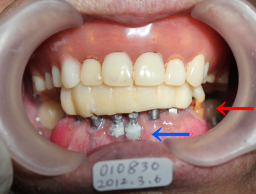

| 91才で44、45にインプラント 2012年03月06日撮影(92才) 術後約6ヶ月 非喫煙者 |

上記のインプラント部分を拡大 高齢で歯磨きが上手に出来ないので 歯垢(プラーク)が歯やインプラント部分に 付着。 |

| 同部分をきれいに磨いてやると 金属色のインプラントがきれいに見えます。 インプラント部分の歯ぐきに炎症なし。 |

| インプラント植立後4年10カ月後 高齢のため最終補綴を入れずにTEK(仮歯)のままです。 仮歯で状態がよければ2〜10年は持ちます。 壊れた時に最終補物を入れるか再度TEKを作ります。 2016年01月09日撮影(96才) どんなにプラークがついてもインプラント周囲炎は起こりません。 |